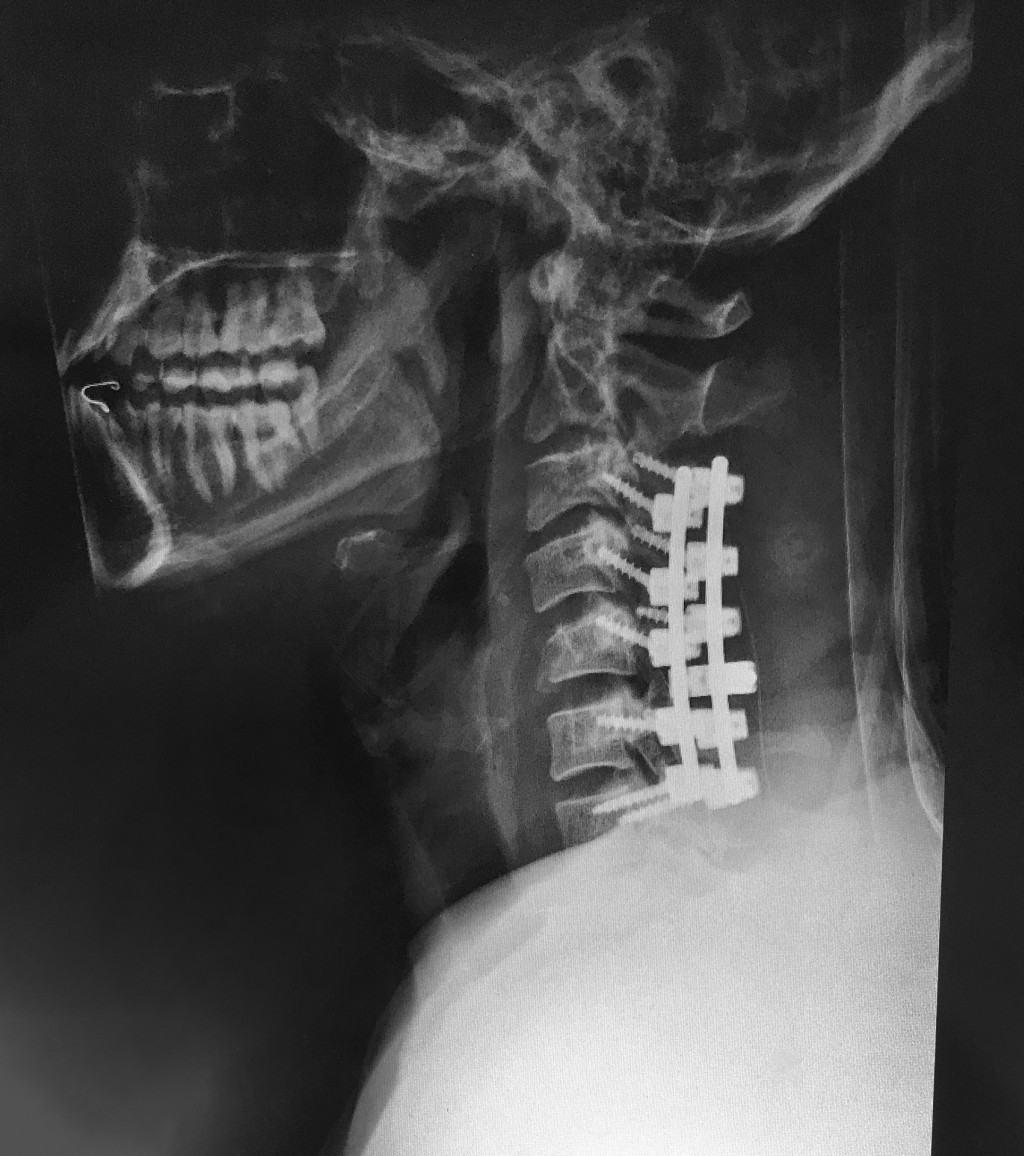

Wrist, ribs, collarbone, and toe — that doesn’t sound too bad — but then there’s that ol’ broken neck. A spinal fusion is deemed the best way forward. “The C-5 vertebrae is the one that impinged the spinal cord — or got jammed into the spinal cord,” says Phil, explaining the extent of the fusion. “The C-4 and C-6 were also shattered, so they fused C-3 through C-7.” It all makes for an X-ray you can’t turn away from.